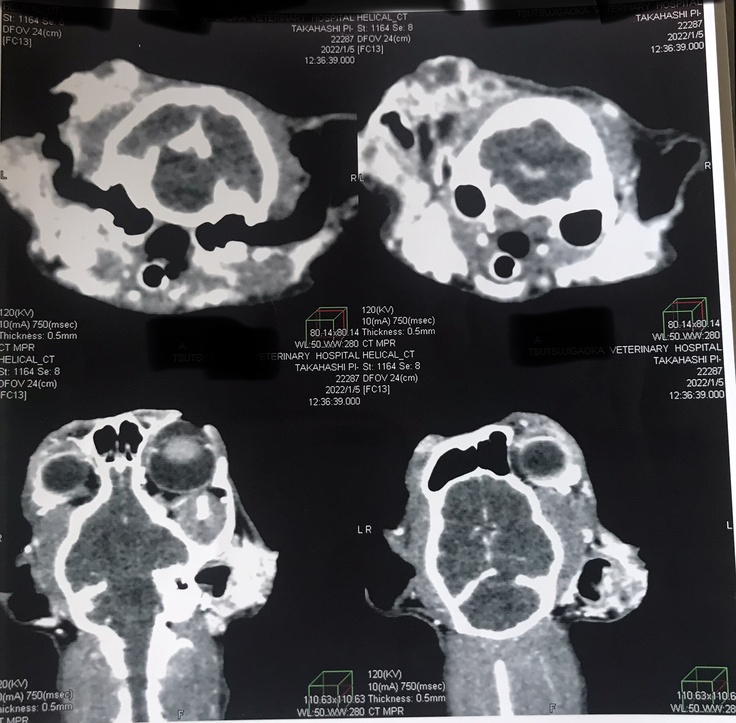

検査の結果、扁平上皮癌と診断され1月5日に手術をする事になりました。

2022年1月5日手術の日。

左耳摘出、右耳半分以上を切除する大変な手術でした。

そして8月21日の検査の結果、目、喉、首、耳に扁平上皮癌の再発が確認されました。